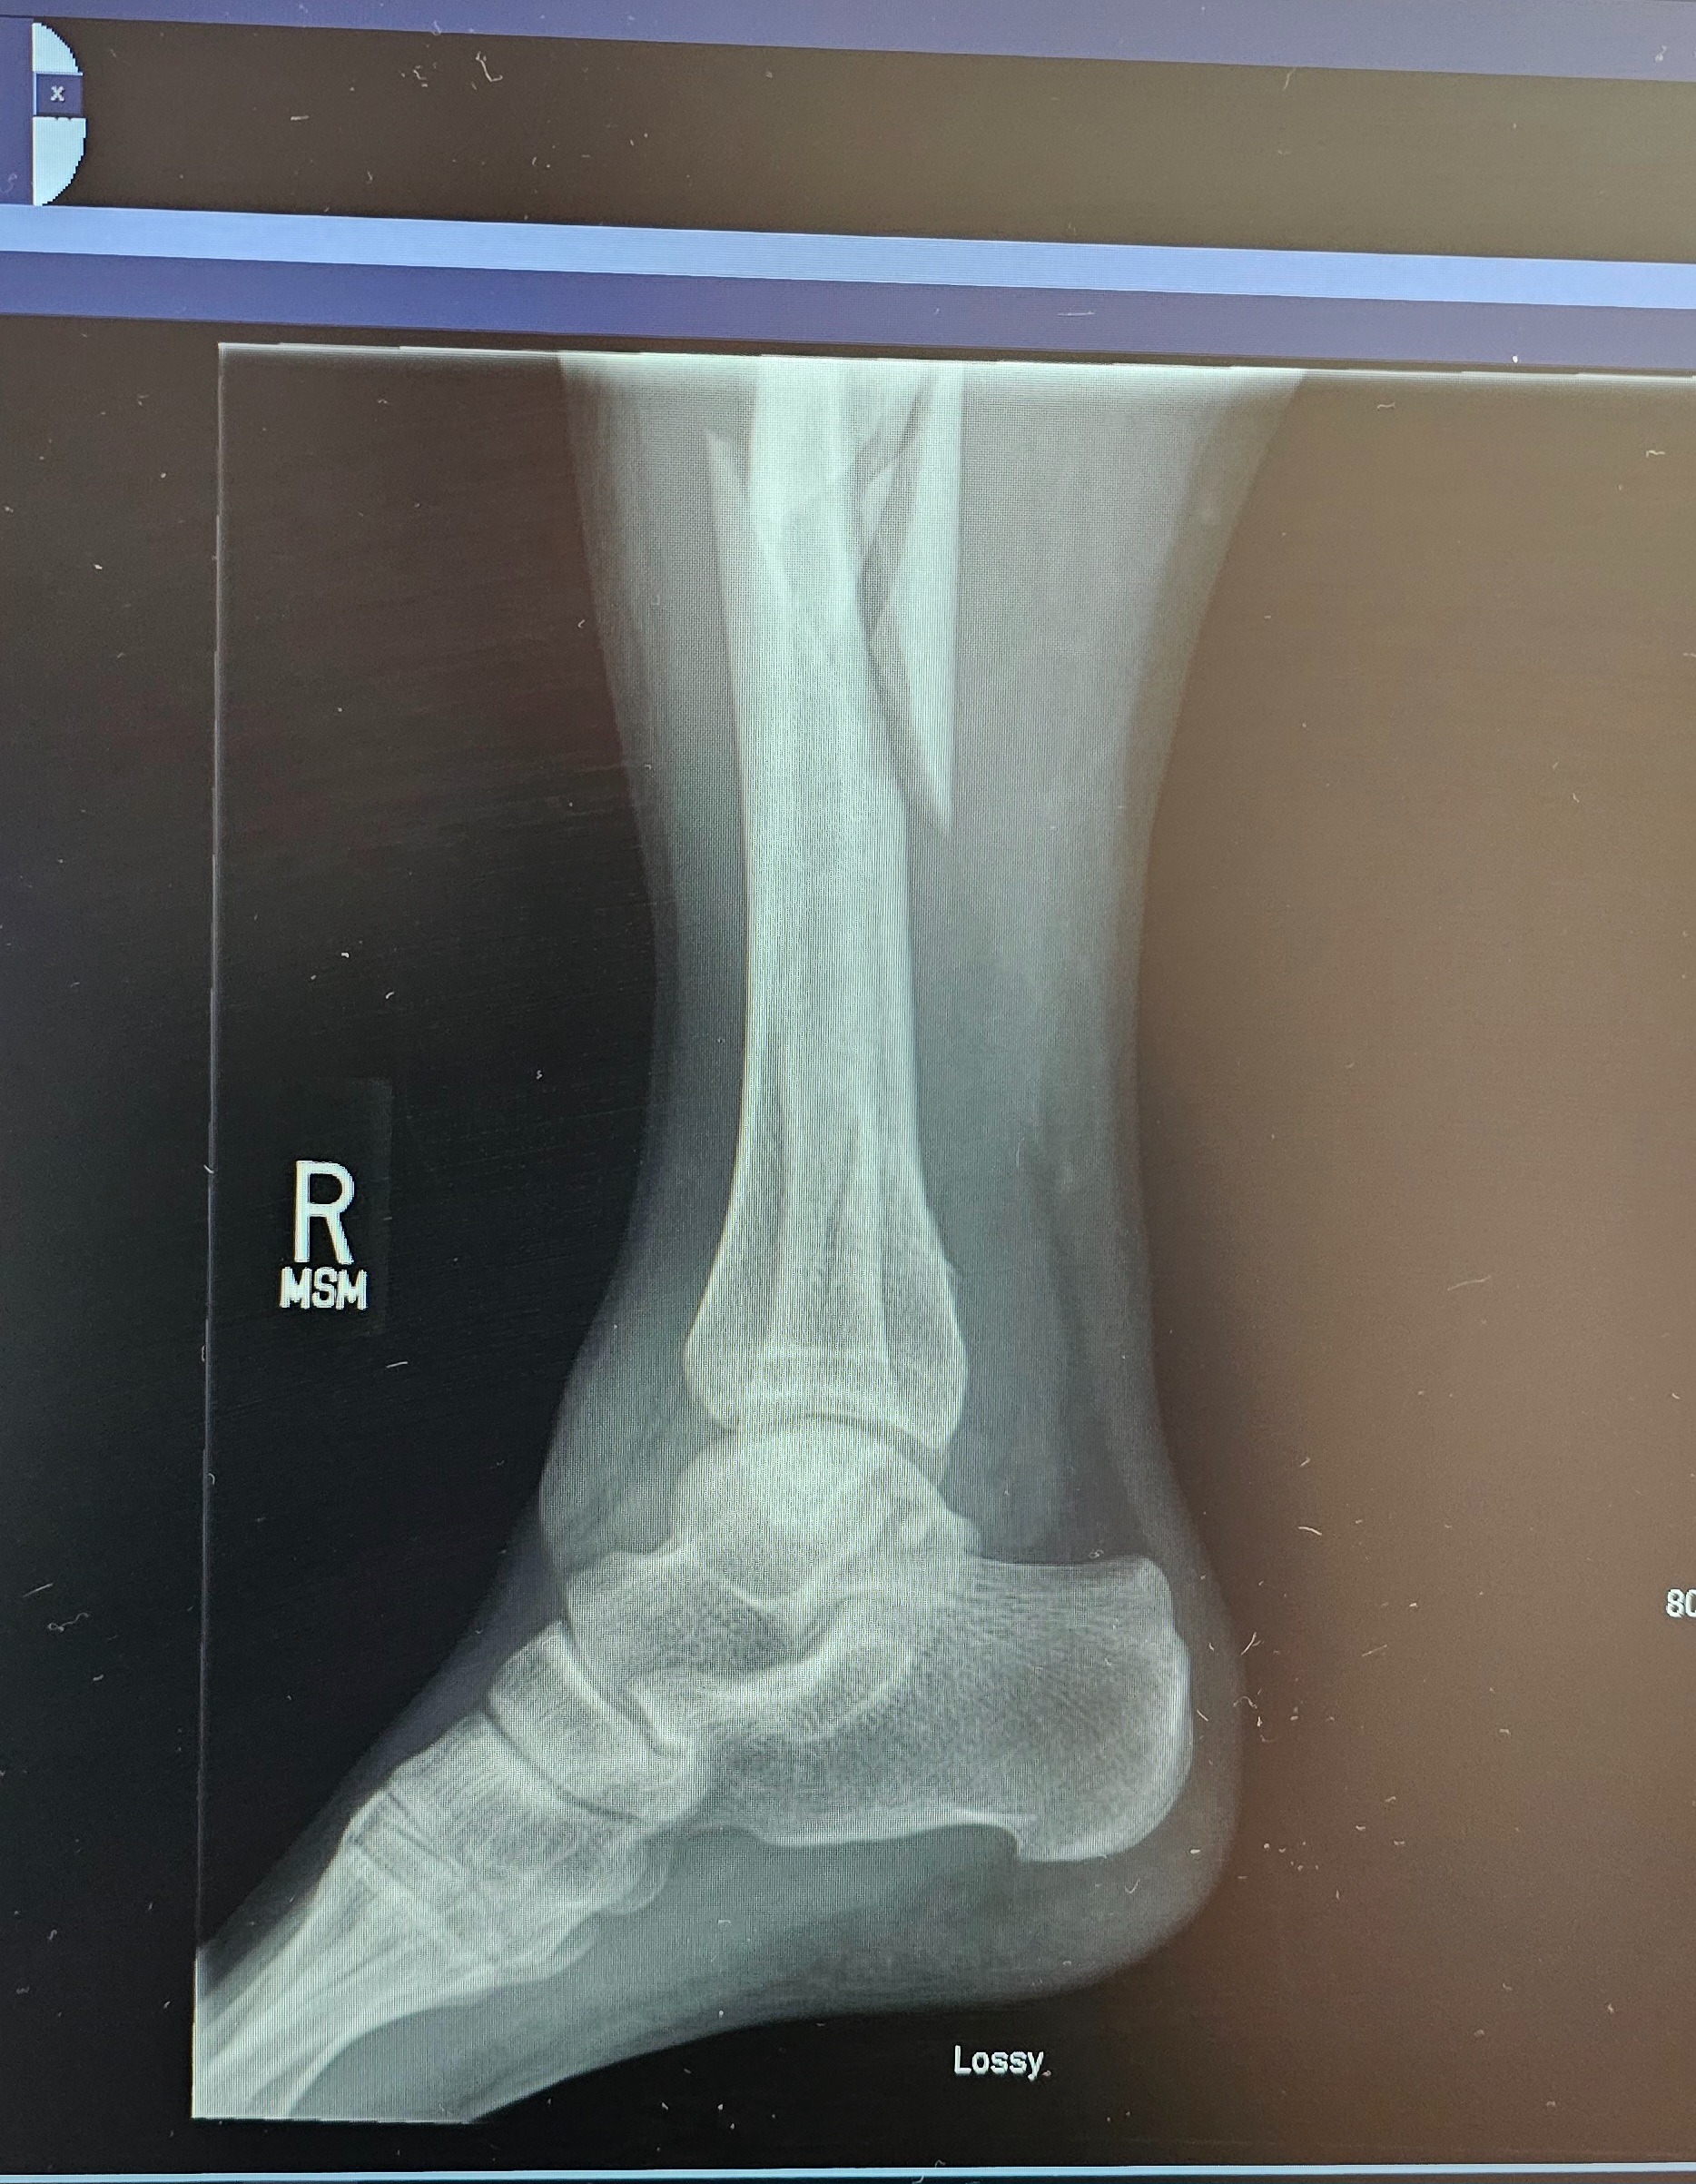

I’ve now been in the hospital for a week, recovering from surgery for a broken tibia, fibula, and ankle. The doctors say I can’t put any pressure on my leg or foot for at least eight weeks. I don’t have health insurance or any job benefits, and my bills are piling up—rent, car payments, and daily expenses. I’ve worked in landscaping for eight years, and it’s devastating to think I could lose everything I’ve worked for. I never thought I’d be in a position to ask for help, but I’m facing the possibility of losing my home and everything I’ve built. I’m doing everything I can to get assistance, but it’s not easy, and I’m running out of options.